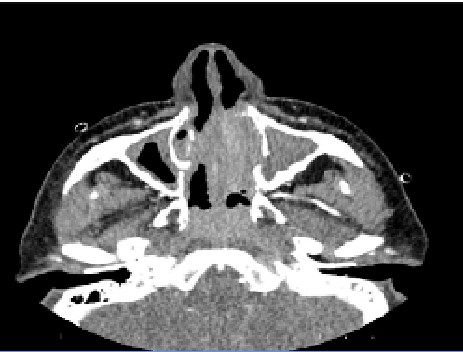

The patient, who has been under observation for approximately one year, presented to us with newly developed skin lesions due to the lack of regression in symptoms during follow-up. Lesions were observed on the distal tibia in front of the ankle, characterized by scattered, intense, pink-red petechial-style spots, and the formation of plaques by their combination (Figure 2). Mild coarse rales were present upon auscultation of the respiratory system. Other system examinations were normal. Blood pressure: 130/70, pulse: 105, respiratory rate: 20, saturation: 91. Total IgE was 3990, and peripheral blood eosinophils were 63% (1800). ANA, RF, and other collagen markers, as well as p-ANCA and c-ANCA, were negative. Parasitological examination of the stool yielded negative results. Echocardiography and abdominal ultrasound were evaluated as normal. Sinus CT revealed widespread mucosal thickening and opacifications related to secretion in the paranasal sinuses (Figure 3). A skin biopsy showed eosinophil-rich vasculitic changes, consistent with Churg-Strauss syndrome (CSS). The patient, diagnosed with CSS based on clinical, laboratory, and pathological findings, was started on cyclophosphamide treatment and is currently under our follow-up.

Figure 3. Widespread mucosal thickening and opacifications related to secretion in the paranasal sinuses